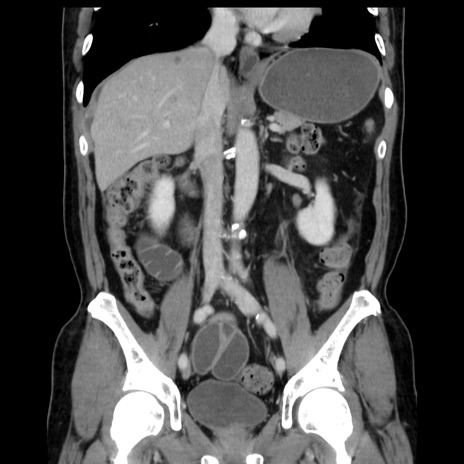

症例16(冠状断像)

【症例】 70歳代男性

【主訴】 腹痛、嘔吐

【現病歴】 約1ヶ月前より間欠的に腹痛と嘔吐あり、当院消化器内科を受診したところCTで多発する肝臓のLDAを指摘され、精査中であった。以降は消化器症状は安定していたが、2日前より嘔気と腹痛があり、同日より排便・排ガスが消失した。改善認めず、 本日、救急外来を受診した。

【既往歴】 大腸ポリープ切除後。

【身体所見】意識清明・会話良好、BT 36.3℃、BP 127/80mmHg、 P 80bpm、腹部:膨満あり、平坦・軟、上腹部正中および下腹部正中に圧痛あり、反跳痛なし、筋性防御なし。

【データ】WBC 7200、CRP 0.77